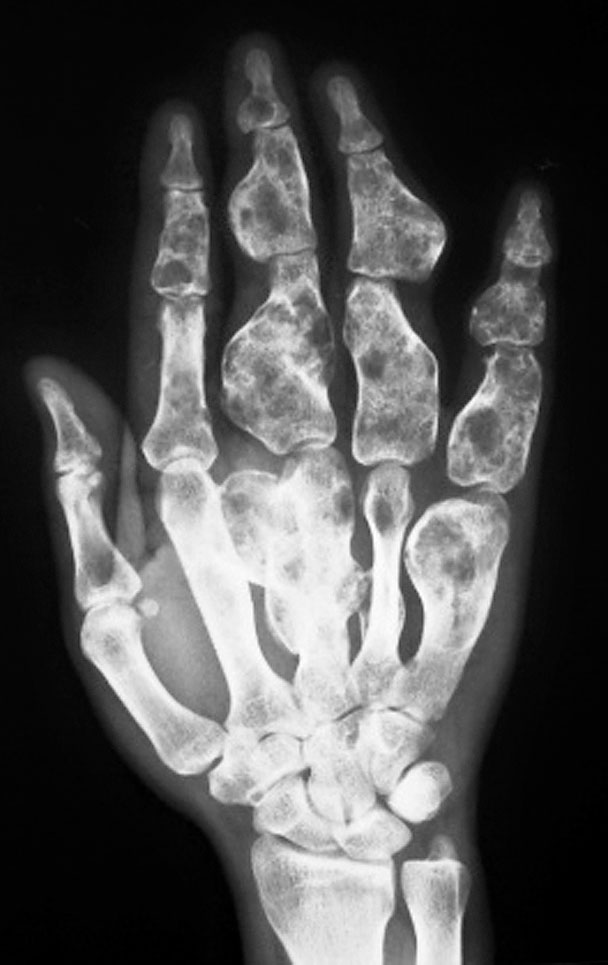

4.骨性肿物

(1)骨软骨瘤病(图1-2-35)。

图1-2-35 右侧桡、尺骨骨软骨瘤病

(2)内生软骨瘤病(图1-2-36)。

图1-2-36 右手内生软骨瘤病